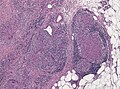

Sarcoidosis-like granulomas in a lymph node. H&E stain. | |

| LM | well-formed granulomas often with few surrounding lymphocytes ("naked"), usually non-necrotizing |

- Granulomata, well-formed, non-necrotizing. ‡

- Usu. minimal (lymphoid) inflammation; sarcoid granulomas are known as "naked granulomas".[8][1]